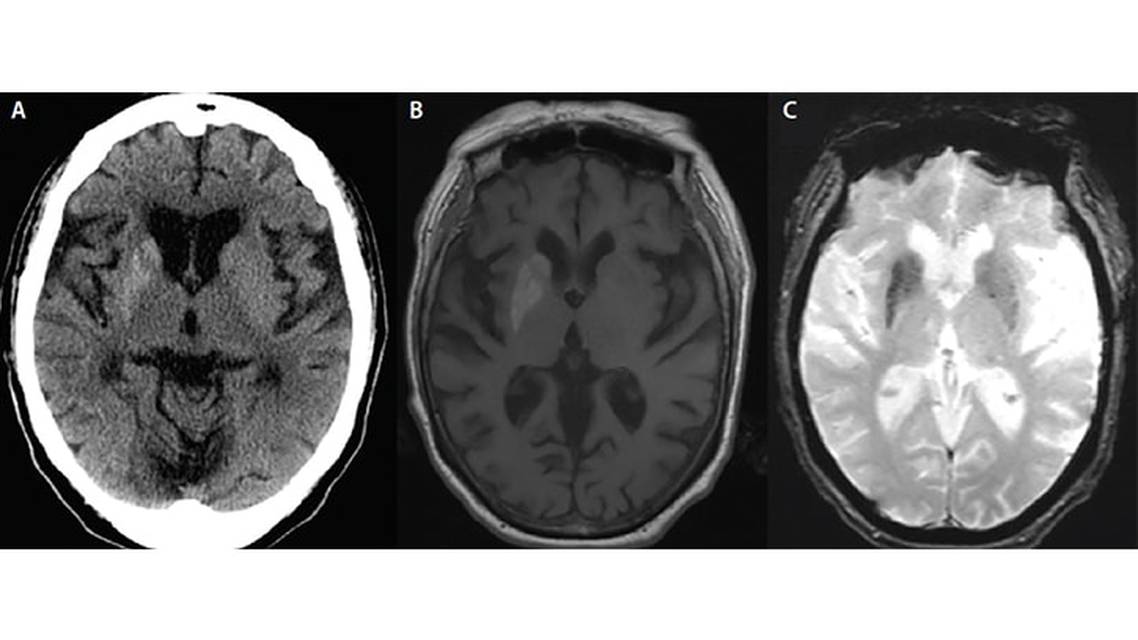

Findings of Ms. B’s noncontrast head CT were initially interpreted as showing an “acute right basal ganglia hemorrhagic infarction” (Figure 1A), and she was admitted to the neuroscience critical care unit for further monitoring. Her brain MRI findings revealed T1 hyperintensity of the right caudate, putamen, and globus pallidus, with gradient echo (GE) hypointensity of the bilateral caudate, putamen, and globus pallidus (Figure 1B and 1C). Ms. B’s imaging studies did not appear consistent with an acute hemorrhage and did not correlate with a prior history of strokes, current arterial or venous thrombosis, or a cranial neoplasm. Re-evaluation of these atypical images suggested a metabolic etiology.

Characteristic imaging findings include hyperintensity on T1-weighted MRI and hypointensity on GE/subtraction-weighted imaging (SWI) within the putamen most prominently, but also in other associated basal ganglia structures. Associated hyperdensities can be seen on noncontrast head CT, although more often than not these are associated with the acute hyperglycemia and not seen chronically in the months following the initial insult. People with NK HB-HC are frequently mistaken to have had a vascular injury such as an acute ischemic stroke or intracerebral hemorrhage given the acute clinical findings and peculiar imaging correlates.